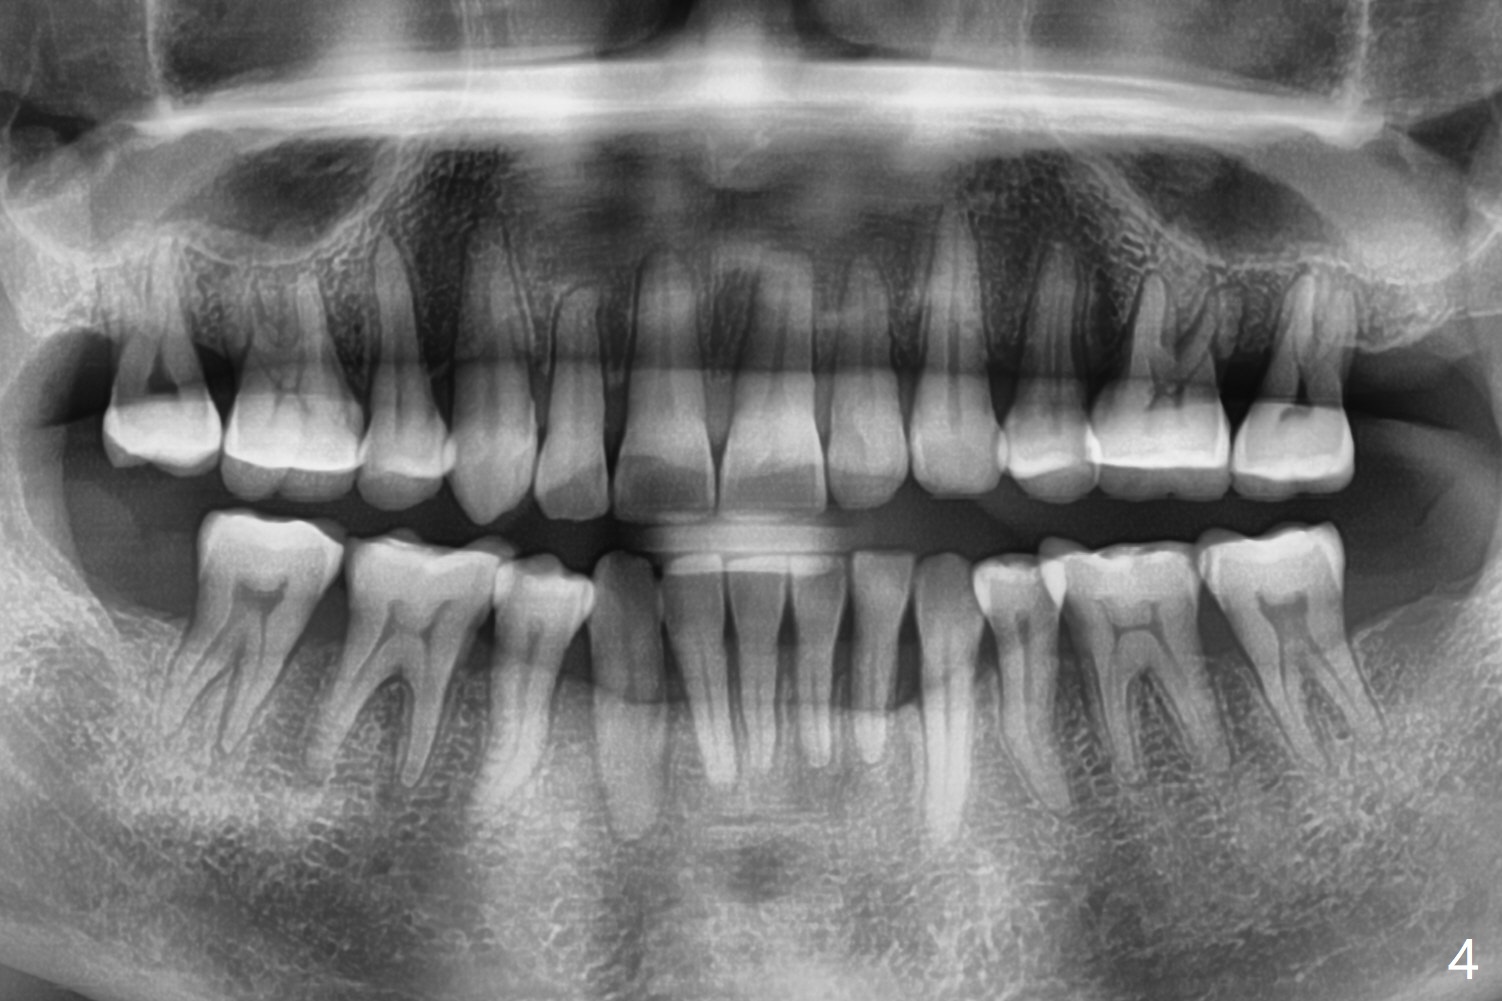

The treatment lasts 1 years 4 months (Fig.4).